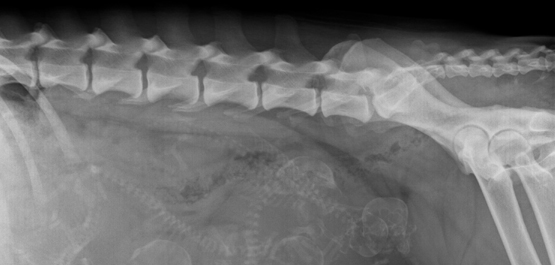

Röntgen:

Mit Hilfe der Röntgentechnik können Knochen- Skelett und Weichteilstrukturen abgebildet und Abnormalitäten schnell erkannt werden. Bei besonderen Indikationen können Reihenuntersuchungen mit und ohne Kontrastmittel durchgeführt werden. Unsere digitale Direktradiografie ermöglicht es uns, die Röntgenaufnahmen sofort mit Ihnen auf dem Computerbildschirm zu besprechen. Auf Wunsch können die Röntgenbilder auch auf CD gebrannt werden.